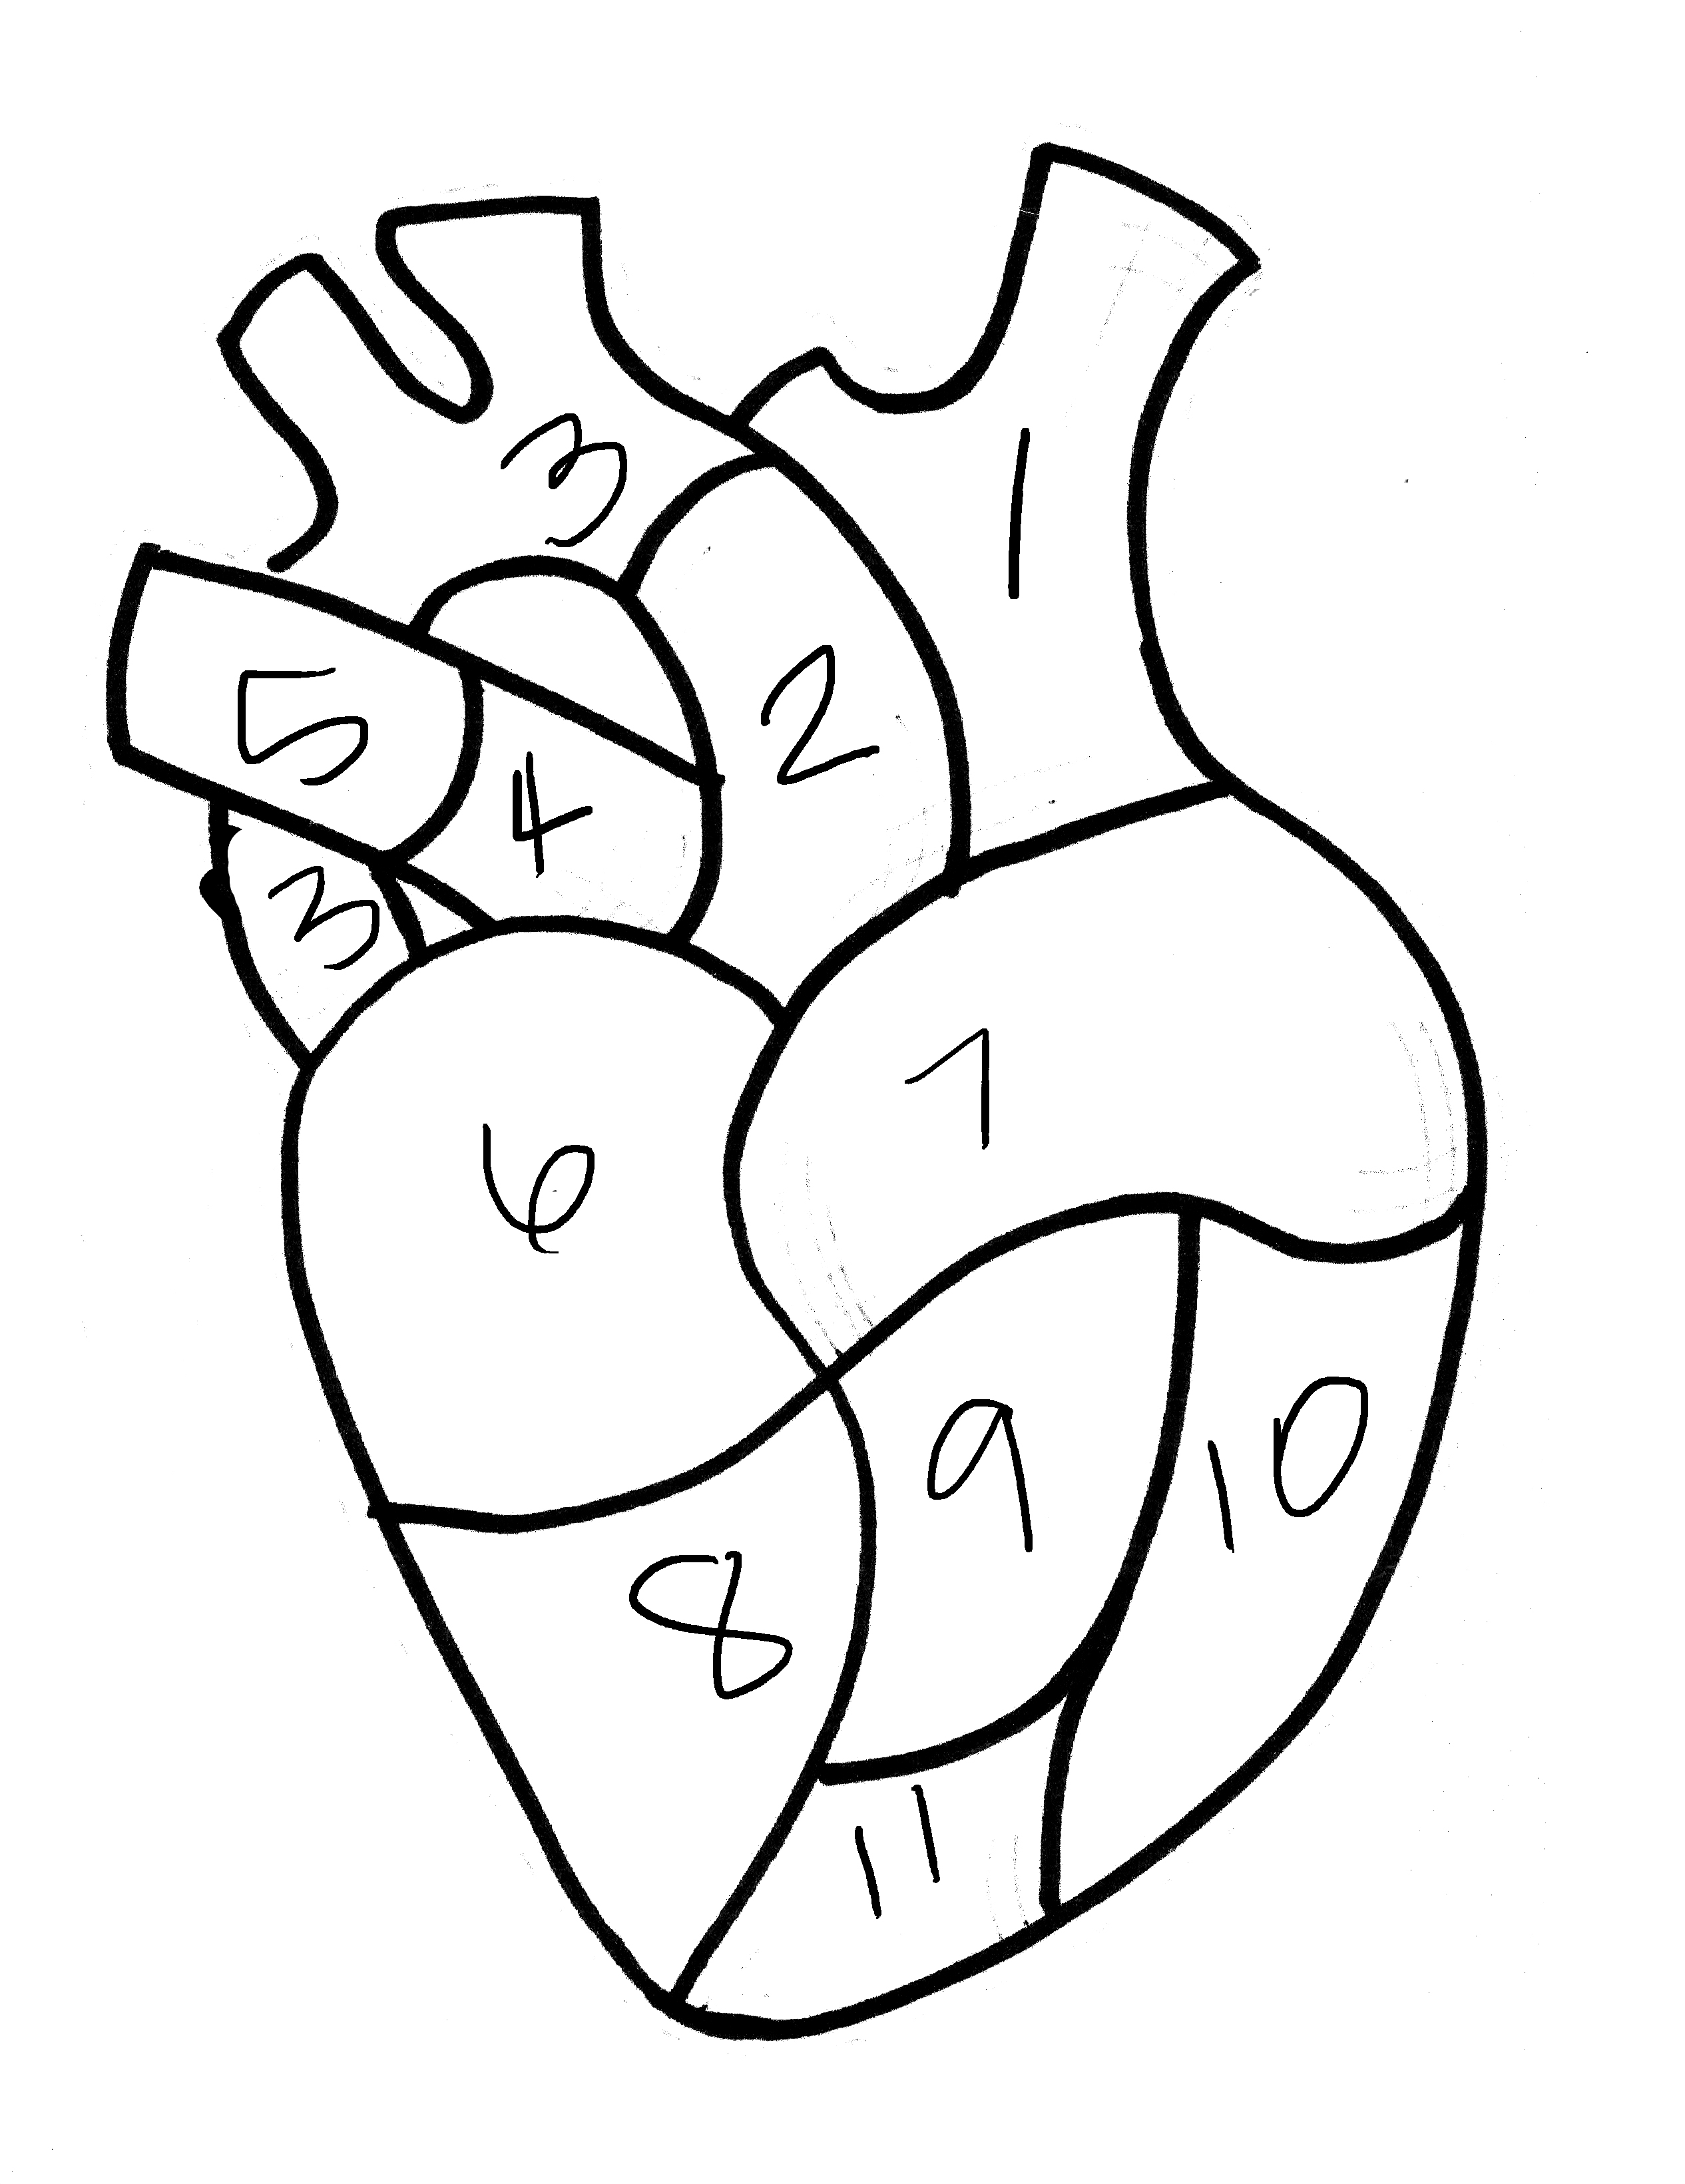

921x690 Anatomical Heart Coloring Pages

620x875 Anatomy Coloring Pages Heart

2550x3300 Anatomical Heart Coloring Page

608x786 Anatomy Of The Heart Coloring Pages Heart Anatomy Coloring Pages

618x921 Coloring Pages Extraordinary Anatomical Heart Outline. Anatomical

600x450 Heart Anatomy Coloring Pages Heart Anatomy Coloring Pages